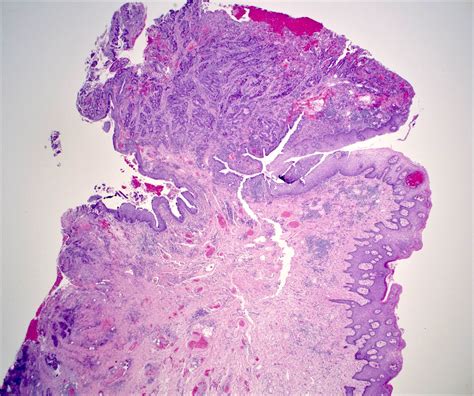

Thrombosed Piles Images: A Visual Guide

Visual aids can be invaluable in understanding and diagnosing thrombosed piles. Thrombosed piles images can help individuals recognize the signs and symptoms of this condition. Below is a table highlighting key visual indicators:

Visual Indicator Description

Swelling A noticeable lump or swelling around the anus.

Discoloration The affected area may appear blue or purple.

Redness The skin around the anus may be red and irritated.

Bleeding Small amounts of blood may be visible on toilet paper or in the stool.

Recognizing these visual indicators can help individuals seek timely medical attention and improve the chances of successful treatment.

Thrombosed Piles Images